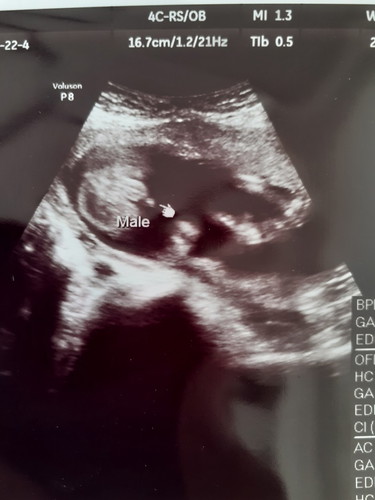

19W3Dจากผลซาวด์คุณหมอ2ท่านความเห็นขัดกันคะคนหนึ่งบอกว่าผู้ชายอีกคนบอกว่าไม่ใช่จู๋แต่เป็นสายรกจะเชื่อใครดีค่ะงงไปหมดเลย

ในใบซาวด์แม่ก็บอกเพศ ตรงคำว่า male คือเด็กผู้ชายค่ะ น่าจะได้ผู้ชายตามที่หมอบอกค่ะ ถ้าได้ผู้หญิงจะขึ้นเป็นคำว่าFemale

บ้านนี้ชายค่ะ ของเราเป็นรูปแบบนี้

มันมีหนังไข่ชัดอยู่ น่าจะชายค่ะ

ไม่อยู่ตรงกลาง น่าจะเป็นสายรกคะ